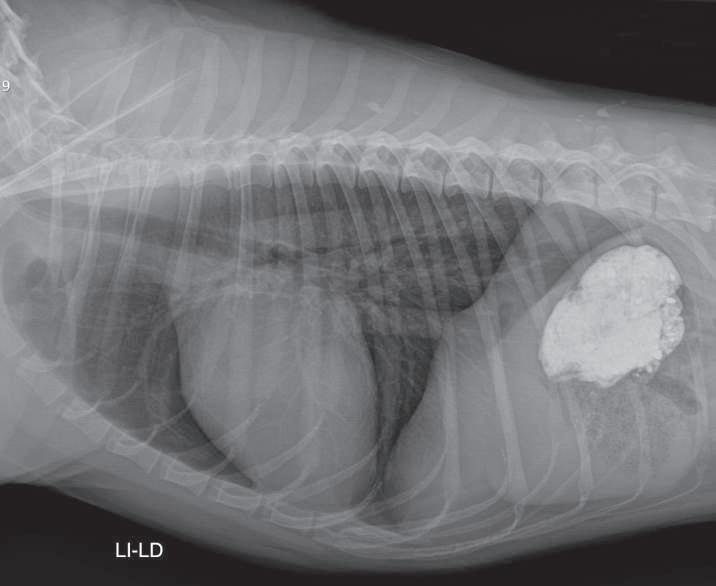

Estudio radiográfico con medio de contraste positivo (sulfato de bario), Li- Ld. Se observa que el medio de contraste pasó en su totalidad al estómago. (p.

Hernia hiatal en un perro, tratada únicamente con gastropexia: Informe de un caso.

Paulina María Carrillo-Solís, Hortensia Corona-Monjarás, Octavio Mejía-Ponce

Hiatal hernia treated in a dog solely with gastropey: a case report. .

tivo, en un intento de diferenciar vómito de regurgitación, se realiza estudio radiográficosimple(sincambiosradiográficos aparentes) (Figuras 1 y 2) yconmediode contraste (sulfato de bario) (Figura 3); se encuentra un tránsito normal del esófago y del estómago.